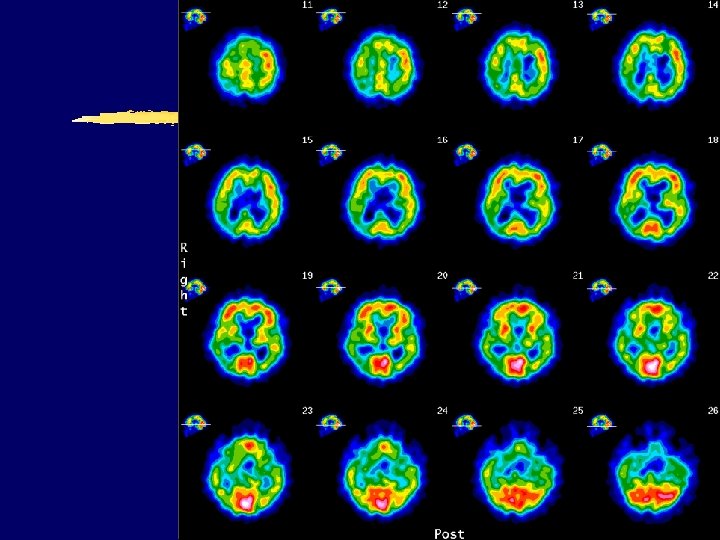

AD – parietotemporal hypometabolism (FDG PET UHC Zagreb) Courtesy of dr. Ratimir Petrović